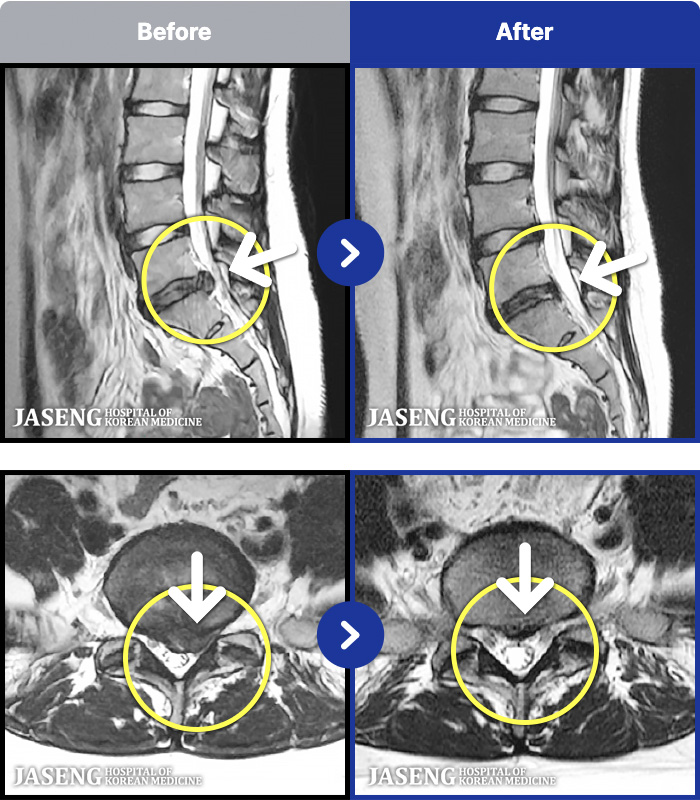

[뱸] 19.11.28~25.05.06